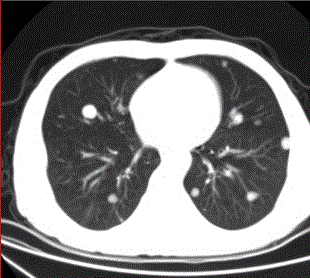

问题 患者男,45岁,因肝硬化、肝癌行肝移植术后6个月,咳嗽2周,来院复查。CR及CT影像如下图。 该疾病的转移途径可以为

选项 A.经肺动脉 B.经肺动脉至淋巴管而后到肺外围 C.经纵隔淋巴结逆流到肺门淋巴结,再经肺内淋巴管到肺外周 D.经胸膜腔 E.经气道 F.经支气管动脉

答案 ACDE